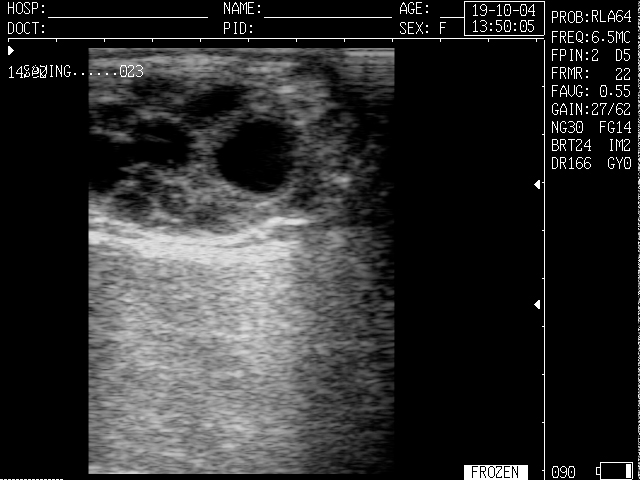

Суть процедуры : с помощью УЗИ можно увидеть и оценить состояние тела матки, шейки матки, яичников, маточных труб (при их патологии) и окружающих их органов. Во время УЗИ измеряются размеры всех доступных для исследования органов, оценивается их структура и соответствие фазе менструального цикла.

Описание процедуры : исследование проводится специальным влагалищным датчиком. Использование его предпочтительнее ввиду лучшей визуализации внутренних половых органов с более тонкой оценкой их структуры.

Все УЗИ-исследования проводятся на современном оборудовании с определением кровотока в органе и образованиях (с ЦДК-цветным дуплексным сканированием). Например образование(узел или какое-либо уплотнение) , который активно кровоснабжается, требует особого внимания. Все это позволяет точно поставить диагноз и своевременно направить на лечение